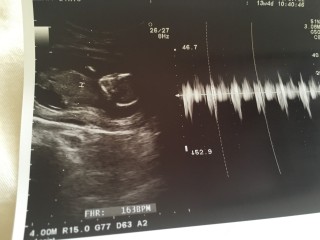

激しい頭痛と腹痛で 妊婦健診、1週間前に急遽 みてもらいました(;_;) 心配して行ったけど 心拍ばくばく!元気でした。 また会えるの楽しみー

27gで順調だと言われました。 エコーだと骸骨みたいに見えるけど、こっちを向いて体育座りしてますよと教えてもらいました*^^* 1ヶ月後が楽しみ!